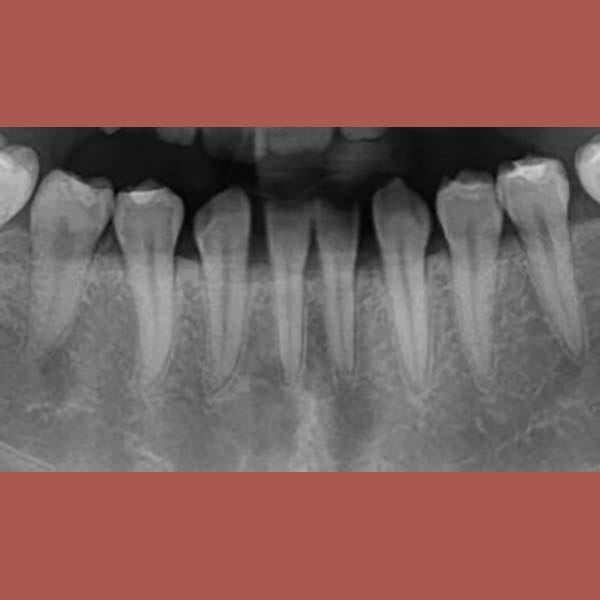

عانت هذه السيدة من وجود عضة عميقة أمامية و غياب خلقي لسنين أماميين سفليين ،بالإضافة لتراكب و عدم ارتصاف الأسنان الأمامية العلوية بشكل جيد – تم فتح مسافة كافية لوضع غرستين سنيتين و تم تصخيح العضة العميقة تقويمياً